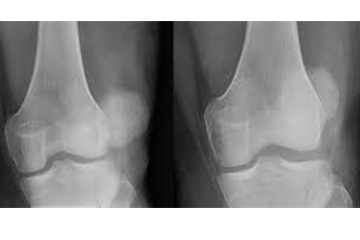

How are they diagnosed?

Luxating patellas can be found on physical examination of your pet, this is why yearly examinations are very important. Your Veterinarian will be able to palpate this abnormality when they put the hind legs through a range of motion. Radiographs will also show abnormalities diagnosing luxating patellas. The severity of this condition is rated on a grade scale from 1-4